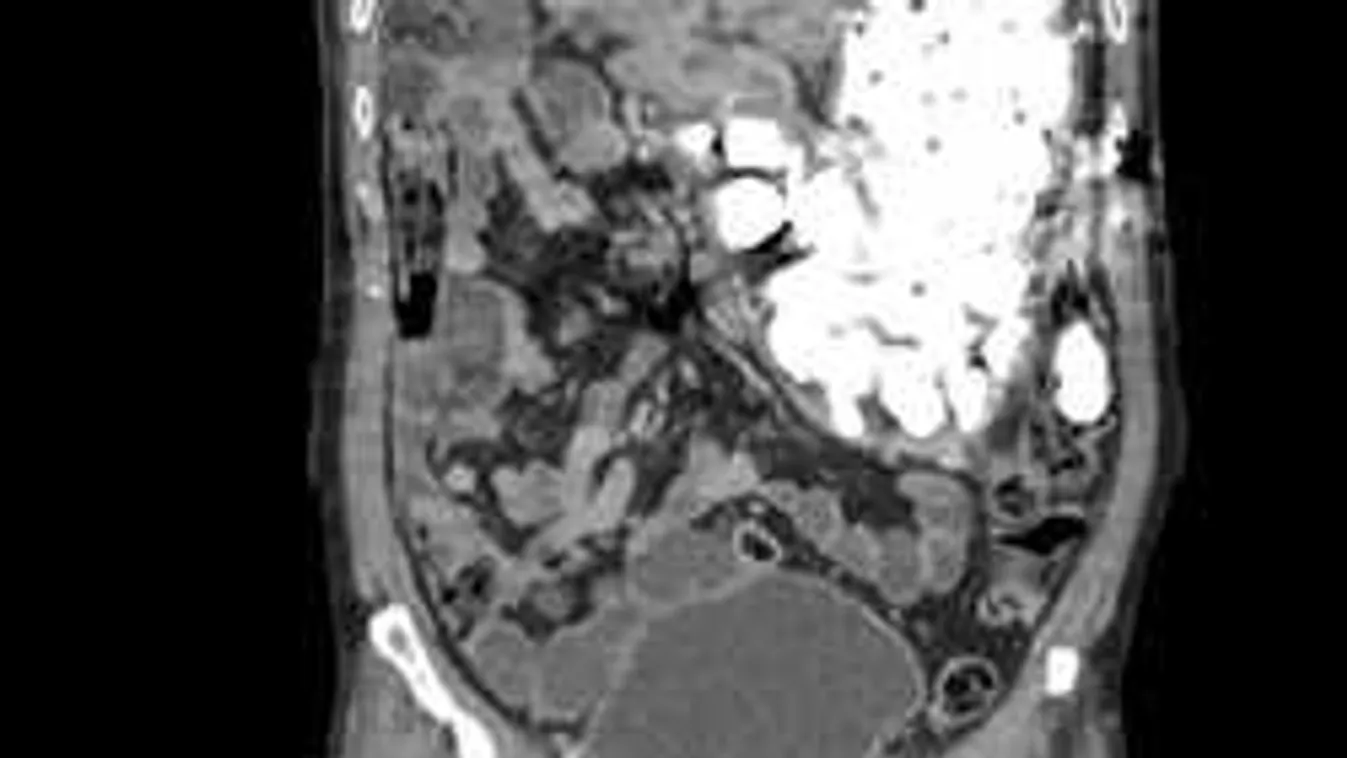

A testidegen tárgyakat először gasztrokópikus eljárással próbálták eltávolítani a koreai férfi nyelőcsövén keresztül. Viszont a beteg gyomrában több száz oda nem illő tárgyat találtak, ezért a szakértőknek végül műtéti úton kellett megoldaniuk a problémát.

"A műtét elkerülhetetlen volt, egyesével képtelenség lett volna kiszedni a nyelőcsövén keresztül azt a sok mindent. Szokatlan eset volt, mivel általában csak kisgyerekek nyelnek le emberi fogyasztásra alkalmatlan tárgyakat, igaz, ők sem ekkora tételben"

- fogalmazott Dr Choi, a műtétet végző orvos, aki 9 nap után engedte haza páciensét.